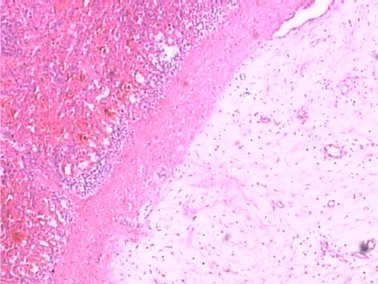

浸润脾脏被膜,如下图2。

图2 HE×40

并浸润结肠壁浆膜层直至肌层,肿瘤内可见出血、坏死、囊性变。瘤细胞胞质界限不清,淡嗜酸性,胞核纺锤形或细长波浪形,染色质分布均匀,少数细胞核略肥胖,似圆形,如下图3。

图3 HE×200